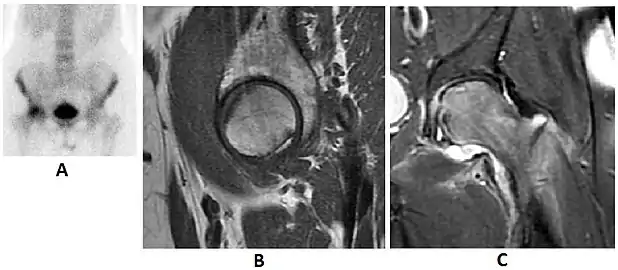

Radiological signs of transient osteoporosis of the hip include localized osteoporosis of the femoral head and neck (Figure 8). Nevertheless, final diagnosis has to be made with MRI to differentiate it from avascular necrosis and from insufficiency or stress fractures of the femoral head or neck. In case of AVN, radiographs can only demonstrate delayed or advanced signs. Staging according to Ficat classification ranges between normal appearance (stage I), slight increased density in the femoral head (stage II), subchondral collapse of the femoral head with or without “crescent” sign (stage III), and advanced collapse with secondary osteoarthritis (stage IV). In the case of stress or insufficiency fractures X-ray sensitivity has been proven to be much lower than MRI, which is currently the gold standard.[1]

Figure 8:

X-ray of a patient with transient osteoporosis of the left hip showing osteoporosis.[1]

Coronal stir imaging in transient osteoporosis, showing diffuse edema.[1]

Scintigraphy (A), sagittal T1 (B), and coronal PD fat sat of a patient with a subchondral fracture of the femoral head with convex shape to the articular surface.[1]

Coronal T1 of a patient with avascular necrosis of the femoral head.[1]

Intra-articular osseous causes of pain include several conditions: avascular necrosis (AVN), transient osteoporosis of the hip (TOH), tumors, and stress or insufficiency fractures. All these entities may present with a pattern of bone marrow edema characterized by decreased signal intensity on T1 weighted images and increased signal intensity on fluid sensitive sequences, such as fat saturated T2-weighted or STIR images. When there is no evidence of a focal lesion associated with the edema pattern, TOH is suspected. When a band of low intensity is seen inside the edematous area, the shape and length of this band become important. It is generally convex to the articular surface in the case of subchondral stress or insufficiency fractures, whereas it is concave, circumscribing all of the necrotic segment, in cases of AVN. When doubts do persist, gadolinium-enhanced MRI tends to show that the proximal portion beyond the band is enhanced in fractures but is not in AVN.[1]